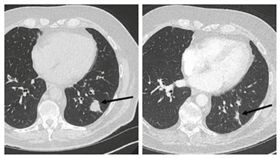

獨/癌末婦吃毒品腫瘤消失?專家:有趣!

外國一名49歲、罹患4期乳腺癌的婦女,在使用大麻二酚...

女乳癌末期嗑大麻迷幻蘑菇!腫瘤消失

大麻在台灣是列管的第二級毒品,但其實它具醫療效果,其...

肺癌阿公拒化療!滴大麻油腫瘤變小了

現代即便醫學發達,對於癌症治療還是無法百分之百掌握。...